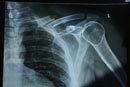

Snapped Collar Bone

Saturday 28Mar09